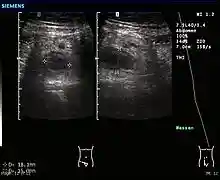

Ultrasound

Ultrasound image of acute appendicitis

Abdominal ultrasonography, preferably with doppler sonography, is useful to detect appendicitis, especially in children. Ultrasound can show the free fluid collection in the right iliac fossa, along with a visible appendix with increased blood flow when using color Doppler, and noncompressibility of the appendix, as it is essentially walled-off abscess. Other secondary sonographic signs of acute appendicitis include the presence of echogenic mesenteric fat surrounding the appendix and the acoustic shadowing of an appendicolith.[45] In some cases (approximately 5%),[46] ultrasonography of the iliac fossa does not reveal any abnormalities despite the presence of appendicitis. This false-negative finding is especially true of early appendicitis before the appendix has become significantly distended. Also, false-negative findings are more common in adults where larger amounts of fat and bowel gas make visualizing the appendix technically difficult. Despite these limitations, sonographic imaging with experienced hands can often distinguish between appendicitis and other diseases with similar symptoms. Some of these conditions include inflammation of lymph nodes near the appendix or pain originating from other pelvic organs such as the ovaries or Fallopian tubes. Ultrasounds may be either done by the radiology department or by the emergency physician.[47]

Ultrasound showing appendicitis and an appendicolith[48]